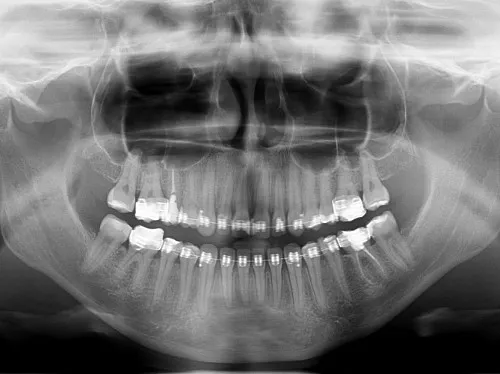

Zdjęcie RTG (pantomogram): co dentysta widzi między zębami i pod dziąsłami?

Zacznijmy od podstaw. Zdjęcie RTG punktowe to małe zdjęcie, które pozwala mi ocenić stan pojedynczego zęba, jego korzeni i otaczających tkanek. Dzięki niemu mogę wykryć próchnicę na powierzchniach stycznych, która jest niewidoczna podczas zwykłego przeglądu, a także stany zapalne wokół wierzchołka korzenia, które często przebiegają bezobjawowo.

Następnie mamy pantomogram, czyli zdjęcie panoramiczne. To badanie daje mi ogólny obraz wszystkich zębów, zatok szczękowych, stawów skroniowo-żuchwowych oraz struktur kości szczęki i żuchwy. Jest absolutnie kluczowe w ocenie zębów zatrzymanych (np. ósemek), planowaniu leczenia ortodontycznego, implantologicznego czy chirurgicznego. To takie "zdjęcie lotnicze" całej jamy ustnej, które pozwala mi dostrzec szerszy kontekst i wzajemne zależności.

Dzięki tym badaniom obrazowym jestem w stanie zdiagnozować wiele ukrytych problemów, które są niewidoczne gołym okiem i często nie dają żadnych objawów, dopóki nie osiągną zaawansowanego stadium. Są to między innymi:

- Torbiele i inne zmiany patologiczne w kościach szczęki i żuchwy.

- Zęby zatrzymane (np. ósemki), które mogą powodować stany zapalne lub przesuwać inne zęby.

- Stany zapalne wokół wierzchołków korzeni, będące często konsekwencją nieleczonej próchnicy lub urazów.

- Resorpcje korzeni, czyli ich stopniowe zanikanie.

- Problemy z zatokami szczękowymi, takie jak stany zapalne czy obecność ciał obcych.